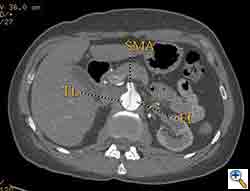

The patient was taken to the hybrid operating suite and a thoracic aortogram was performed. The aortogram confirmed the chronic Type B aortic dissection with a patent false lumen and a fenestration just beyond the left subclavian artery. An intravascular ultrasound (IVUS) was also performed of the entire aortic arch and descending thoracic and abdominal aorta. The IVUS also confirmed that there was an adequate proximal landing zone beyond the left subclavian artery consisting of normal aorta where we would be able to achieve adequate seal of the endovascular stent graft. The septal fenestration began approximately 1.5 cm distal to the left subclavian artery. The true lumen was compressed distally. (Figure 2) The celiac artery appeared to come off the true lumen. (Figure 3) The dissection extended into the superior mesenteric artery and the artery was perfused from both the true and false lumen. (Figure 4) The left renal artery came off the false lumen. (Figure 5) The right renal artery came off the true lumen.